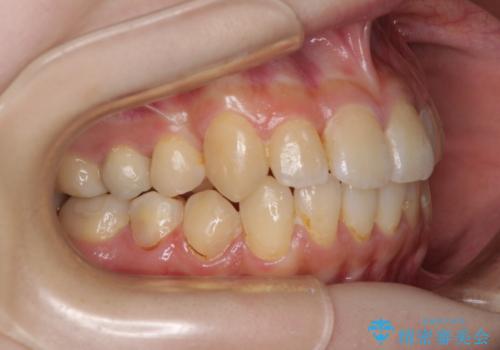

デコボコ歯列をきれいに インビザラインによる矯正治療

- 上下歯列全体のデコボコを気にして来院された患者様です。

主に下顎歯列全体の後方移動とIPR(歯と歯の間を削る)によってデコボコが解消するように設計し、インビザラインにより治療を行うこととしました。

奥歯の知覚過敏が顕著となり、その影響で奥歯の咬み合わせ改善のための顎間ゴムの装着ができず、咬合を仕上げるまでに長い期間を要することとなりました。